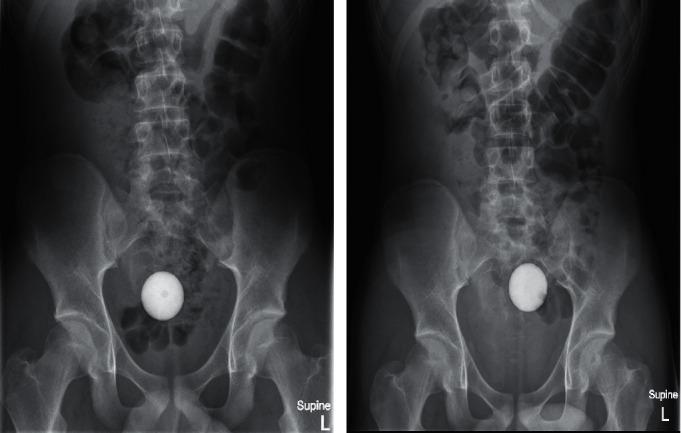

Rectal foreign bodies form a surprisingly frequent cause of presentation to the emergency department. The materials inserted constitute a wide range of size, shape, and texture with each presenting a unique set of challenges. Despite a seemingly innocuous presentation, if not recognised early and managed accordingly, significant complications can develop including obstruction, perforation, and sphincteric injury. The existing doctrines advocate endoscopic intervention after simple measures fail and advise against the use of laxative therapy due to concerns for complications that may arise. The authors of this study challenge this notion, provided certain conditions are met. . We report the case of a 14-year-old boy who inserted a golf ball into his rectum, which subsequently migrated proximally into the sigmoid colon on plain radiographic films. The patient was asymptomatic on presentation, and there was no clinical evidence of bowel injury or mechanical bowel obstruction. Endoscopic removal of the golf ball was pursued under general anaesthesia. Despite protracted efforts, the golf ball was not able to be retrieved endoscopically. In an attempt to avoid aggressive surgery, volume laxatives were administered with successful passage of the golf ball several hours later.

直肠异物是急诊就诊的一个出人意料的常见原因。插入的物品在大小、形状和质地方面多种多样,每种都带来一系列独特的挑战。尽管临床表现看似无害,但如果早期未被识别并进行相应处理,可能会出现严重并发症,包括梗阻、穿孔和括约肌损伤。现有理论主张在简单措施失败后进行内镜干预,并因担心可能出现的并发症而建议不要使用泻药疗法。本研究的作者对这一观点提出了质疑,前提是满足某些条件。我们报告了一名14岁男孩的病例,他将一个高尔夫球插入直肠,随后在平片上显示该球向近端迁移至乙状结肠。患者就诊时无症状,也没有肠道损伤或机械性肠梗阻的临床证据。在全身麻醉下尝试通过内镜取出高尔夫球。尽管经过长时间努力,但仍无法通过内镜取出该球。为避免进行激进手术,给予了大容量泻药,数小时后高尔夫球成功排出。